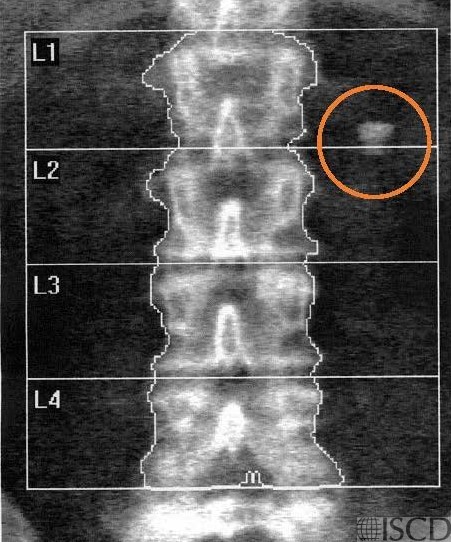

The baseline lumbar spine Hologic scan shows a Darvocet-N100 tablet lateral to L1 on the right (orange circle).

The follow up scan 5 minutes later shows that the tablet has changed in position (orange circle)..

This lumbar spine shows a Darvocet N-100 pill on the baseine image and the position of the tablet 5 minutes later (orange circles).